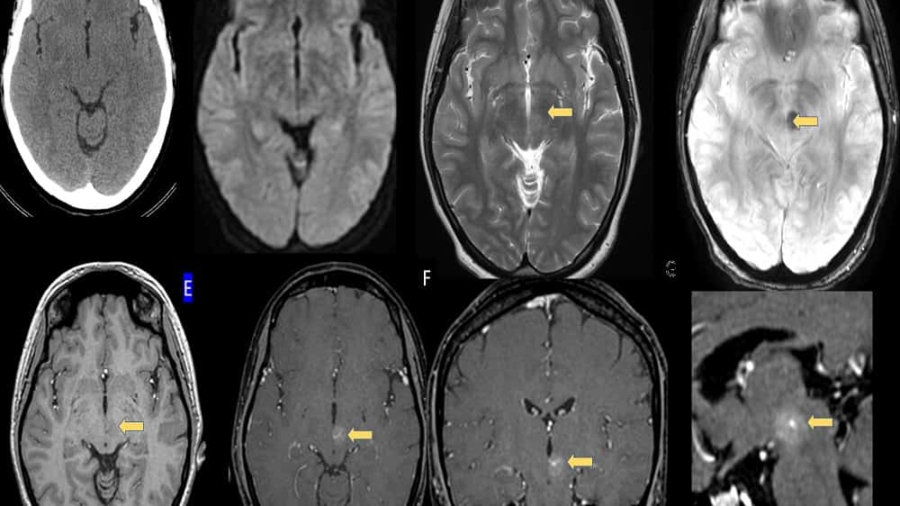

A 31 year old male presented with history of seizures since 2 months. He was treated with anti epileptics and was well controlled. Patient again developed breakthrough seizures. No focal neurological deficits.

Auto immune work up & CSF analysis were unremarkable.